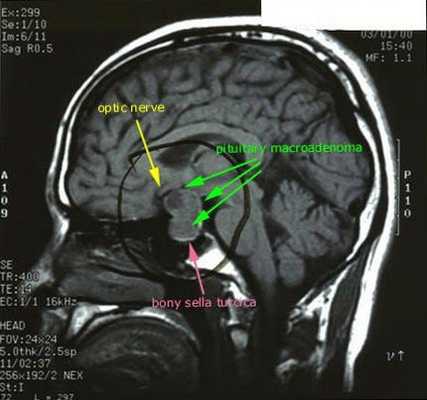

С помощью рентгенографии черепа (турецкого седла) выявляются макроаденомы гипофиза; при КТ и МРТ головного мозга с введением контраста - микроаденомы (в 50-75% случаев). При рентгенографии позвоночника обнаруживаются выраженные признаки остеопороза.

После подтверждённого гиперкортицизма необходимо проведение инструментальных методов исследования (МРТ гипофиза, КТ надпочечников).

![МРТ гипофиза]()

При БИК в 80-85% случаев выявляют микроаденому гипофиза (опухоль до 10 мм), у остальных 15-20% — макроаденому (доброкачественное новообразование от 10 мм). [7]